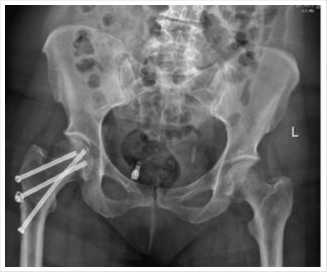

На следующие сутки проведена рентгенография тазобедренных суставов (Рис. 4).

Рис. 4. Рентгенограмма тазобедренных суставов после операции.